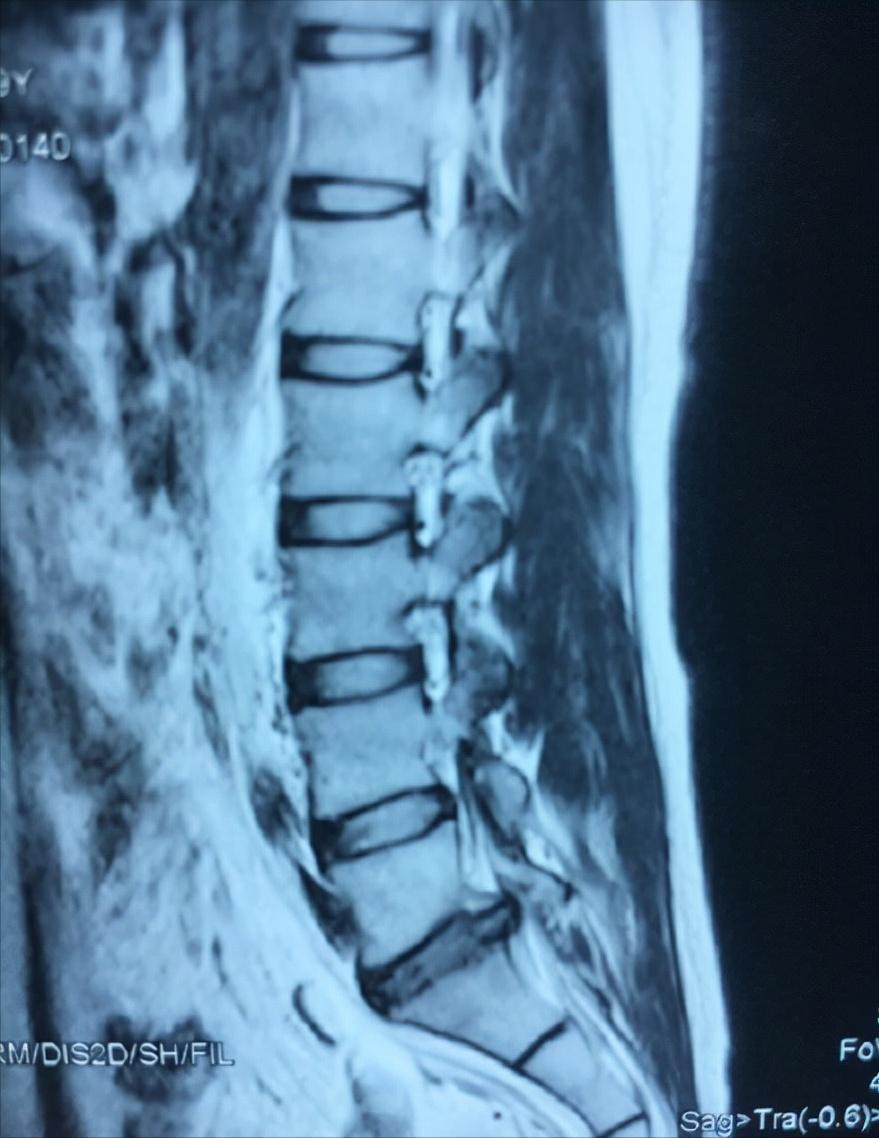

老张接诊过一个腰椎间盘突出的患者, 是一个才刚刚17岁的少年,现在才上高三,患者在去年的时候出现了腰疼和腿疼的症状 ,当时拍的核磁片子,显示患者是腰5骶1向后突出。

仔细看了患者的片子还有诊断结果之后告诉他妈妈,这个情况能治,不用手术,一定会给孩子尽力治疗,孩子还小老张看着也不忍心。 刻诊,患者舌暗红有瘀斑苔白腻,脉弦细。